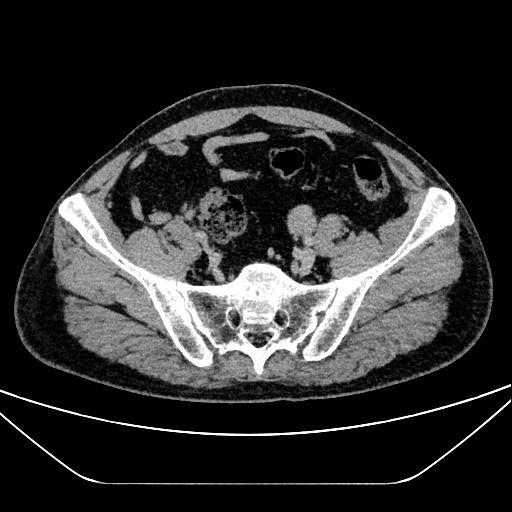

7.上腹部CT平扫增强+薄层(2025-10-30):肝脏、胆囊、脾脏未见异常强化影,胰腺大小形态正常,胰头局部见脂肪低密度影,无异常强化,胰管无扩张;左侧输尿管中段腔内软组织密度影,累及长度约33mm,管径宽约18mm,明显强化,增强扫描三期CT值约81Hu、82Hu、69Hu,其以上输尿管、肾盂肾盏扩张积液,左肾皮质变薄,左肾强化程度减低,排泄期肾盂及输尿管未见造影剂充盈;右肾见直径约3mm小类圆形无强化等密度影,右侧输尿管及肾盂无明显异常,无异常强化影;膀胱、前列腺、精囊腺无异常强化影;腹膜后多发小淋巴结,轻中度强化;右侧肾上腺结合部见直径约9mm等密度结节影,动脉期明显结节状强化,余期呈等密度;

1.左输尿管占位性病变:患者有间断血尿4月余的典型主诉;CT检查提示左侧输尿管中段腔内存在肿瘤性病变,有明确的大小、强化特征,且排泄期肾盂及输尿管无造影剂充盈;术中可见左侧输尿管口水肿伴狭窄,输尿管上段出血水肿、有大量血性液体流出;术后病理检查明确诊断为输尿管浸润性高级别乳头状尿路上皮癌,为该诊断提供金标准依据。

2.左肾积水:CT检查显示左侧输尿管病变上游尿路积水,左肾皮质变薄、强化程度减低;术中及术后病理检查均显示左肾存在肾盂肾盏扩张,符合肾积水的影像学及病理改变,可明确诊断。